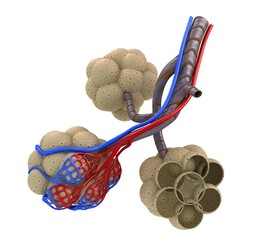

Kun ilma päätyy keuhkorakkulaan, ilman happi siirtyy rakkulan ympärillä olevaan hiussuoneen. Siitä happi jatkaa matkaa verisuonia pitkin sydämen kautta esimerkiksi hauislihakseen.

Samalla kun happea siirtyy keuhkorakkulasta hiussuoneen, myrkyllistä hiilidioksidia siirtyy hiussuonesta keuhkorakkulaan. Hiilidioksidi poistuu keuhkoista uloshengityksessä.